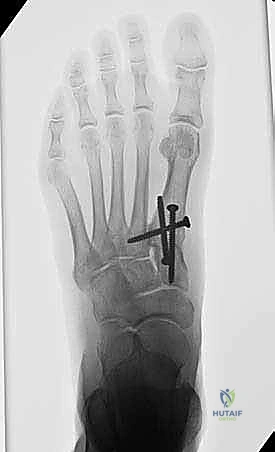

5. التثبيت الداخلي (Internal Fixation)

بعد التأكد من المحاذاة المثالية، يتم تثبيت العظام بشكل دائم. يستخدم الأستاذ الدكتور محمد هطيف أحدث التقنيات العالمية في التثبيت، والتي تشمل عادة مسامير تيتانيوم متقاطعة (Crossed Screws) أو شريحة معدنية متخصصة مع مسامير (Plating System) لضمان أقصى درجات الثبات والضغط بين العظمتين، مما يسرع من عملية الالتئام.

- المتابعة الإشعاعية: يتم إجراء أشعة سينية للتأكد من بدء التحام العظام.

- تحمل الوزن: إذا كانت الأشعة مطمئنة، يُسمح بالانتقال التدريجي لتحميل الوزن الكامل أثناء ارتداء الحذاء الطبي، ثم الانتقال لاحقاً إلى حذاء رياضي واسع ومريح.